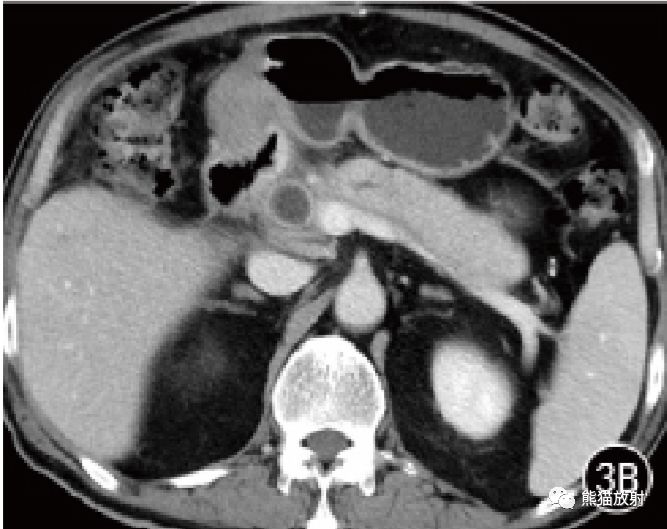

图 2 男,63岁。AIP 胰腺弥漫性病变, CT门静脉期胰腺弥漫性肿胀呈腊肠样,周围见包壳,胰管未见扩张,脾静脉变细狭窄;门静脉期冠状位重组胰腺段胆管狭窄,管壁增厚 。